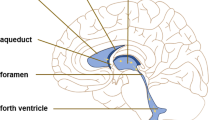

With the advent of new imaging modalities and experimental tools, it is now possible to dissect the various points of obstruction and further classify hydrocephalus into distinct pathologies. Recently, Rekate et al. proposed a contemporary classification of hydrocephalus based on a flow circuit model. The Rekate model, much like Dandy’s, rests on two simple assumptions: CSF is either overproduced (e.g., choroid plexus papillomas) or underrecycled via flow obstruction at the level of the foramen of Monro, aqueduct of Sylvius, outlets of fourth ventricle, basal cisterns, arachnoid granulations, or other points of absorption [15, 16]. Simplifying hydrocephalus into a disease of overproduction or impaired CSF absorption, it becomes an intuitive extension to assume that water channels are key players in the pathophysiology of this disease. Aquaporins are highly expressed at known points of CSF production and absorption such as the choroid plexus and extrachoroidal sites and ependymal cells, glia limitans interna, and CSF circulation at the cortical subarachnoid space like glia limitans externa, subpial zone, and meninges. In addition, aquaporin-4 is highly expressed at the end feet of the astrocyte processes that are part of the blood–brain barrier (BBB) [3, 7–9, 17–22].

Aquaporin-4 is the most abundant water channel in the brain [7, 8, 20, 35]. Main areas of high distribution include the glia cells at the junction of fluid and brain parenchyma, at BBB and blood–CSF barriers like ependymal cells, glia limitans interna (astrocyte processes and ependyma bordering brain and subarachnoid CSF at the subpial zone), and glia limitans externa (astrocyte processes bordering brain and ventricular CSF) [7]. The location-specific distribution of AQP4 around tissue interfaces that are close to CSF and thus water (ventricles, subarachnoid space) indicates that these channels are significant for the regulation of water physiology in these areas. Specifically, aquaporin-4 is located at the perivascular end feet processes of astrocytes that form the blood–brain barrier (Fig. 1). Other areas of AQP-4 in brain are the cerebellum, the supraoptic and suprachiasmatic nucleus of the hypothalamus, hippocampal dentate gyrus and areas CA-1 and CA-3, neocortex, nucleus of stria terminalis, and medial habenular nucleus [7]. Mobasheri et al., using a tissue microarray approach, showed that AQP4 is expressed in meningeal tissues in humans [20]. This observation, in conjunction with the documented presence of AQP4 at the glia limitans externa, the glial area at the brain surface under the pia mater, in many species could possibly indicate an active role of AQP4 water channel at the cortical subarachnoid space or at the surface brain parenchyma in regulating the concentration of water and ions in the CSF.

Bloch and colleagues used a kaolin injection model in cisterna magna of mice in order to reproduce obstructive hydrocephalus in wild-type mice and AQP4-knockout mice [45]. The kaolin injection model is a well-established model of progressive acute obstructive hydrocephalus in rodents [46]. The authors assessed parameters of ICP, ventriculomegaly, brain parenchymal water content, and 5-day survival rate between mice groups over a specific time frame [45]. The AQP4-knockout mice demonstrated significant ventriculomegaly; ICP was increased and brain water content was also increased by 2–3% [45]. The increased brain water content in AQP4-knockout mice indicated the existence of “hydrocephalic edema.” In 5 days, 84% of the wild-type mice survived compared to 66% of AQP4 knockouts, indicating that hydrocephalus induced by kaolin injection was much more severe in mice that do not express AQP4. The authors constructed a mathematical computational model of kaolin-induced hydrocephalus using the data obtained from these experiments. The mathematical model reconfirmed the observations obtained and predicted that the severity of hydrocephalus would be much more reduced when AQP4 expression increased. A protective role of AQP4 concerning hydrocephalus was suggested in the article based on the above observations. Since AQP4 is expressed at brain–CSF (ependyma and glia limitans under the subarachnoid space) and blood–brain barriers the authors proposed a significant role for AQP4-mediated transparenchymal CSF absorption in cerebral vasculature in cases of hydrocephalus [45]. The significant role of aquaporin-4 in the clearance of excess brain water and specifically vasogenic brain edema has been documented in multiple studies [7, 13, 24, 47–57]. Feng and colleagues published an interesting observation in AQP4-knockout mice [58]. In a series of 612 AQP4 knockouts, a percentage of 9.6% demonstrated obstructive hydrocephalus. The site of obstruction was identified and was located at the level of cerebral aqueduct leading to aqueductal stenosis. Histological studies at the site of stenosis revealed marked ependymal disorganization. The authors attributed the presence of sporadic obstructive hydrocephalus in a subset of AQP4 knockouts to AQP4 polymorphisms that could contribute to the development of aqueductal stenosis [9, 58]. The kaolin injection model has also been used in rats to study the expression of AQP4 after these animals develop obstructive hydrocephalus [59–61].